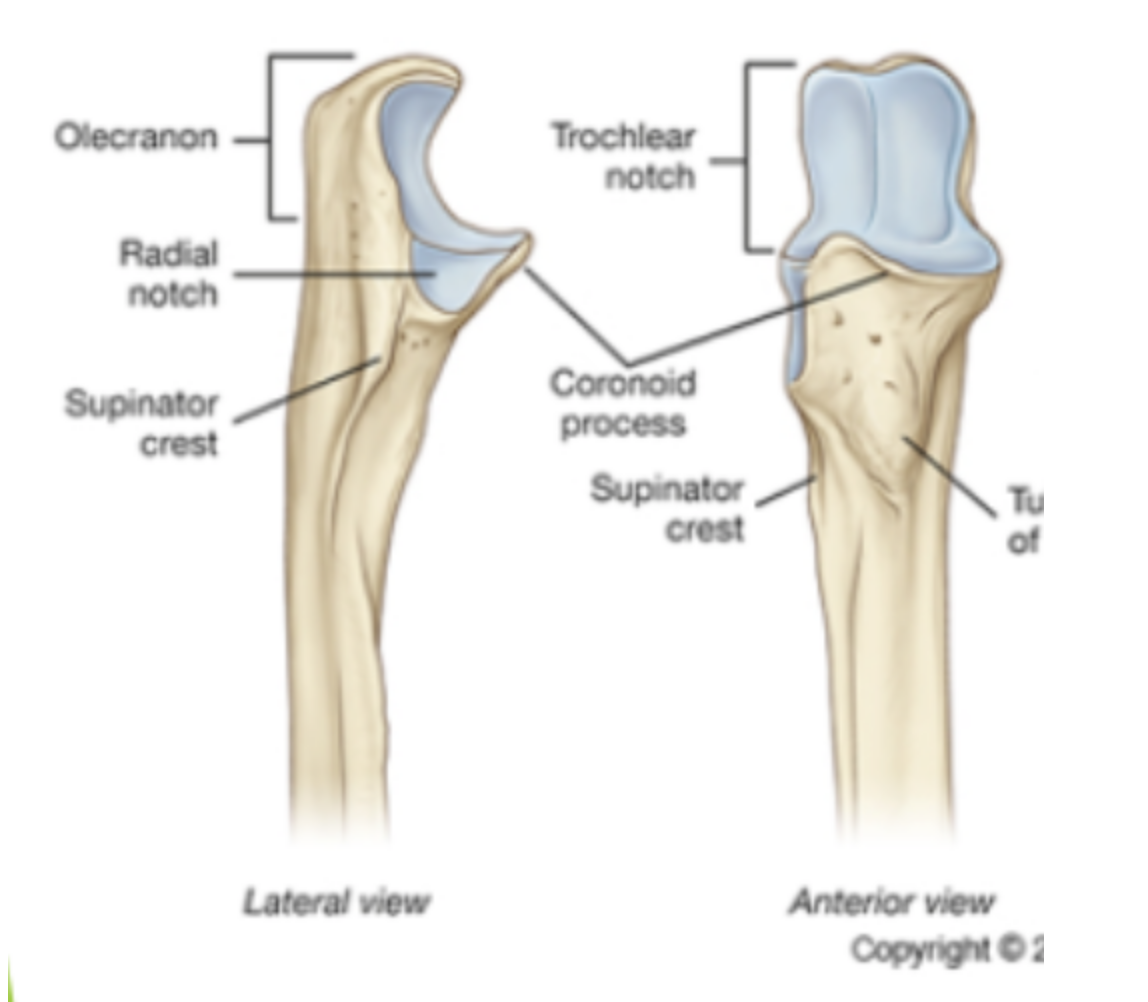

label the parts of the ulna

the suppinator attatches to the suppinator crest

anconeus attatches to roughening for acconeus

Ulna bone

1) Olecranon process

2) Trochlea notch (hosts trochlea of humerus)

3) Radial notch

4) Coronoid Process

5) Ulnar tuberosity